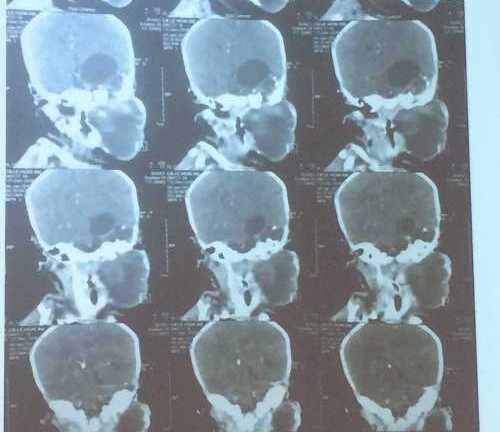

Bướu quái chứa xương và tóc hiếm gặp ở bé gái 20 ngày tuổi

Thay vì mổ hai lần như dự kiến, các bác sĩ ung bướu và ngoại thần kinh Bệnh viện Nhi đồng 1 đã phối hợp bóc trọn vẹn khối bướu quái hiếm gặp trên thế giới cho bé.